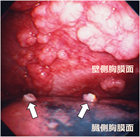

1. 胸腔鏡で腫瘍が確認されない最も早期の胸膜中皮腫である”mesothelioma in situ(前浸潤性中皮腫)” の存在は以前から知られていたが、『WHO分類 第5版』に初めて明記された。

1. 早期の胸膜中皮腫と反応性中皮細胞増生(反応性中皮過形成)の病理像は類似し、良悪の鑑別は慎重に行う必要がある。BAP1免疫染色、CDKN2A遺伝子の中皮腫でのホモ接合性欠失の検出が鑑別に役立つ。